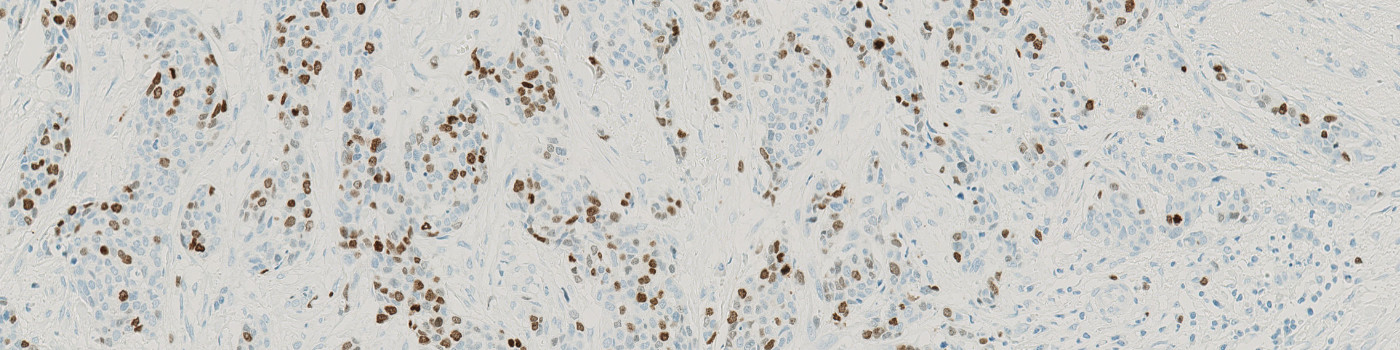

Figure 1

Breast tissue stained with Ki-67 where tumor is present.